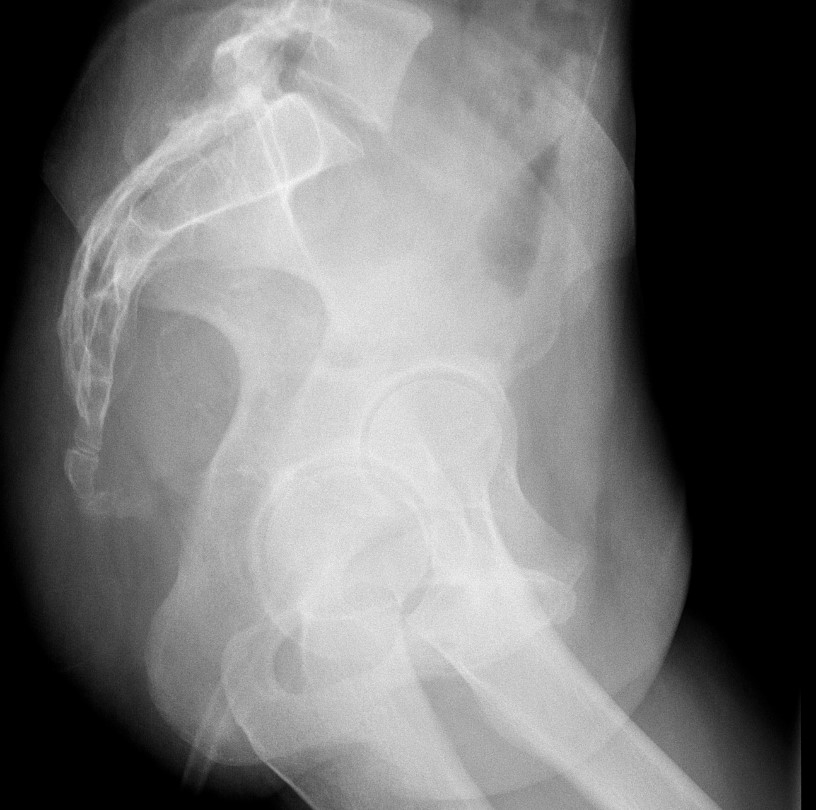

- When reviewing the preliminary scout film, you should see multiple surgical chain sutures in the pelvis

(key image 31)

(key image 32).